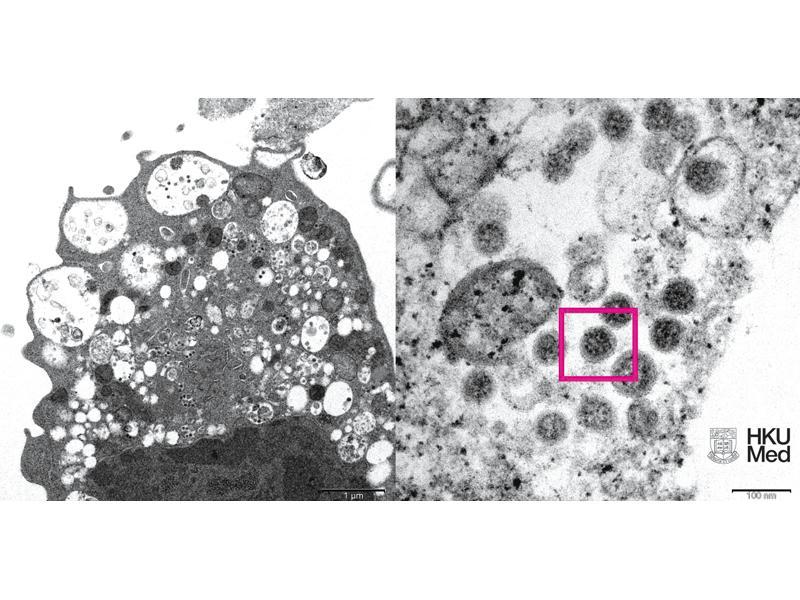

港大醫學院揭Omicron面貌

另外,香港大學醫學院昨公布照片,研究人員將病毒注入細胞,電子顯微鏡下Omicron跟以往如Delta等變種病毒株一樣,在相同位置攻擊細胞,未有進一步證據顯示Omicron威力有增強。港大醫學院將Omicron注入猴腎細胞(Vero E6),攻毒後以低倍電子顯微鏡所見,細胞受損,腫脹囊泡,囊泡內含有黑色小病毒顆粒;高倍電子顯微鏡就反映病毒顆粒表面呈現皇冠形的刺突蛋白。